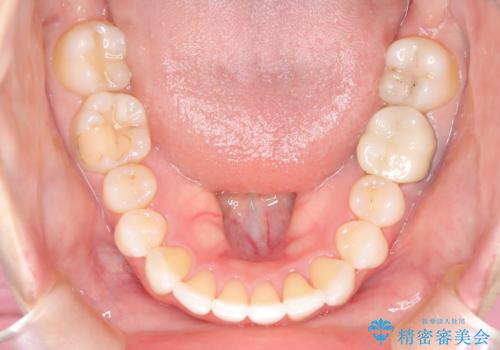

- 前歯のガタつき、変色を主訴に来院された患者様です。術前診査のCT撮影にて、変色した前歯の根の先に病巣があることが判明しました。そこで、マウスピースによる矯正治療と、前歯の根管治療、かぶせ物のやり直し治療を並行して行いました。

一般的に矯正専門歯科では、矯正以外の口腔内管理はほかの歯科へお願いされることが多いです。当院では、虫歯治療や根管治療の知識が豊富なドクターが矯正治療を担当いたしますので、安心して通院していただくことができます。